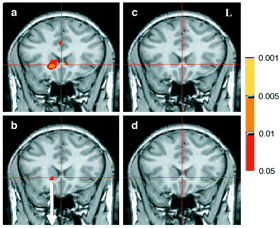

•   Das beidseitig am Boden des Mittelhirns (anat.: ventral) verlaufende Striatum (Streifengebilde), insbesondere sein Nucleus accumbens (Nacc)2,3,8,10), der zusammen mit dem Dopamin- und µ-Opioid-System unsere Lust-, Belohnungs- und Glücks-Leit- und Steuerzentrale ist.

(Bild unten): Vier fMRT-Scanner-Aufnahmen (coronal Aufnahmen, Durchsicht von vorne), während wir finanzielle Belohnungen (oder Bestrafungen) erwarten. Nur in der ersten Scanner-Aufnahme, links oben (a), während wir in freudiger Vorwegnahme, Erwartung und Vorfreude größer werdende Belohnungen (größere Geldgewinne, mehr Geld) erwarten, ist der Nacc aktiver3,10).

Die drei dimensionalen Ebenen des Gehirns 4 fMRT-Scanner-Aufnahmen vom Nucleus accumbens während der Erwartung größer werdender finanzieller Belohnungen und Bestrafungen

© 2001 by Knutson, NIH/NIAAA / USA